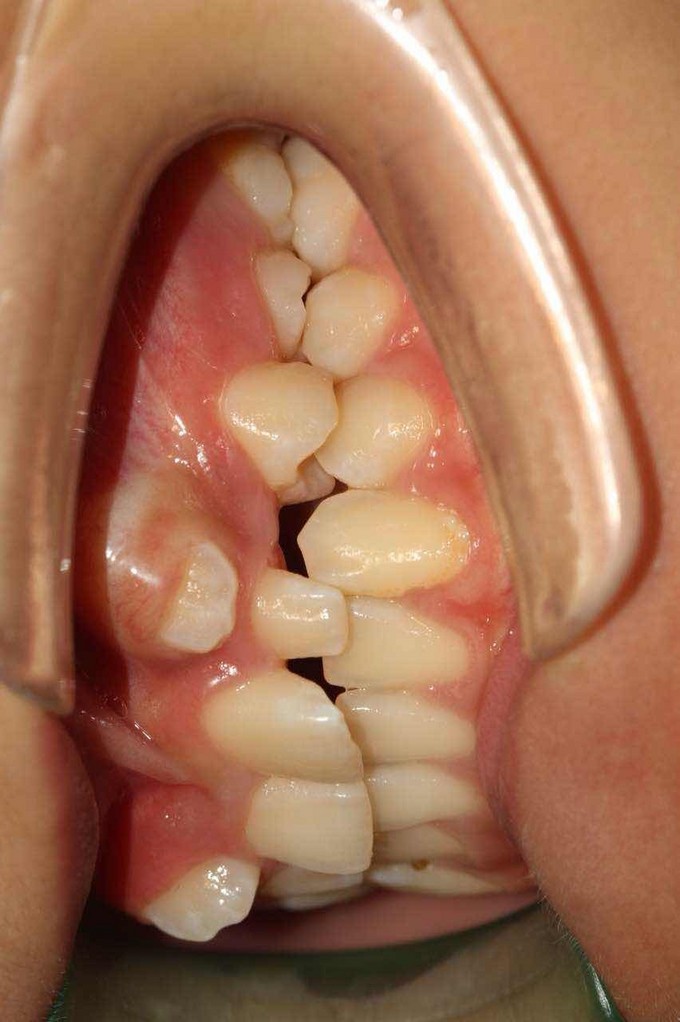

尖牙错位,2过小牙

患者:女,19岁,主诉牙齿不齐,希望矫治。 检查:13根在11和12之间,23根在22唇侧,12和22为过小牙